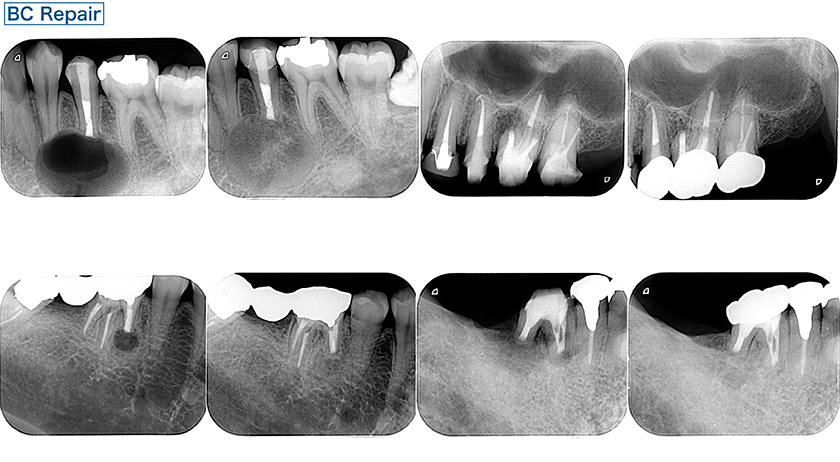

再根管治療

オンデマンド配信期間 2026年6月24日(水)~7月8日(水)

講演のポイント

・エビデンスをもとに根尖病変の病因、治癒のタイムラインを整理

・再根管治療を行うか否か、その判断基準と考え方

・ポスト・ガッタパーチャ除去の理論と安全に行うための実践的テクニック

・穿孔修復、破折ファイル除去に対する意思決定と具体的手技